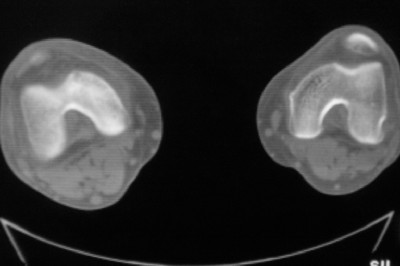

标题: CT8024:会诊!!!男 60 岁 双漆关节疼痛半年,进行性加重 [打印本页]

患者男 60 岁 双漆关节疼痛半年,进行性加重.

右股骨内髁关节面下多个不规则小囊变,边缘有明显硬化边,.......考虑: 1.关节面下骨囊变.  2.类风湿关节炎?   3.血友病?

右侧髁间隆突变尖,软骨下假囊肿形成,结合病人年龄较大,首先考虑退行性骨关节病。关节周围软组织未见明显异常,病人单单一双膝关节出现症状,不太支持类风湿性关节炎,可结合化验室检查。